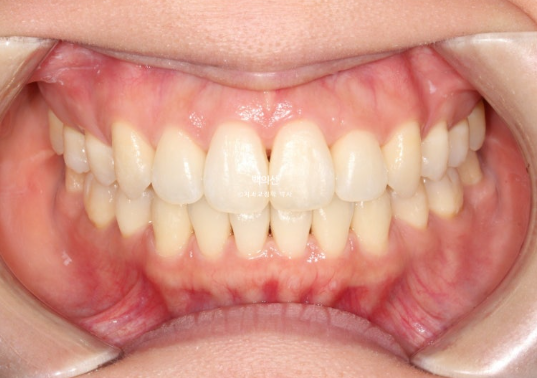

이제 전 후 비교해보겠습니다.

총 치료기간은 2년 6개월, 재제작은 총 2회 했습니다.

23.01~25.07